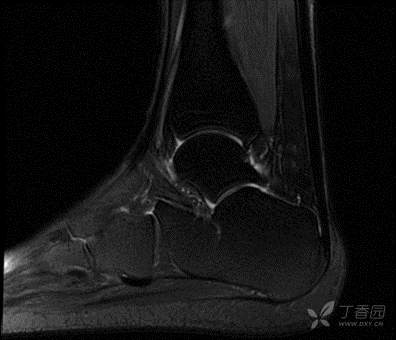

1. 踝关节核磁:左踝关节退行性变,跟腓韧带损伤变性可能。